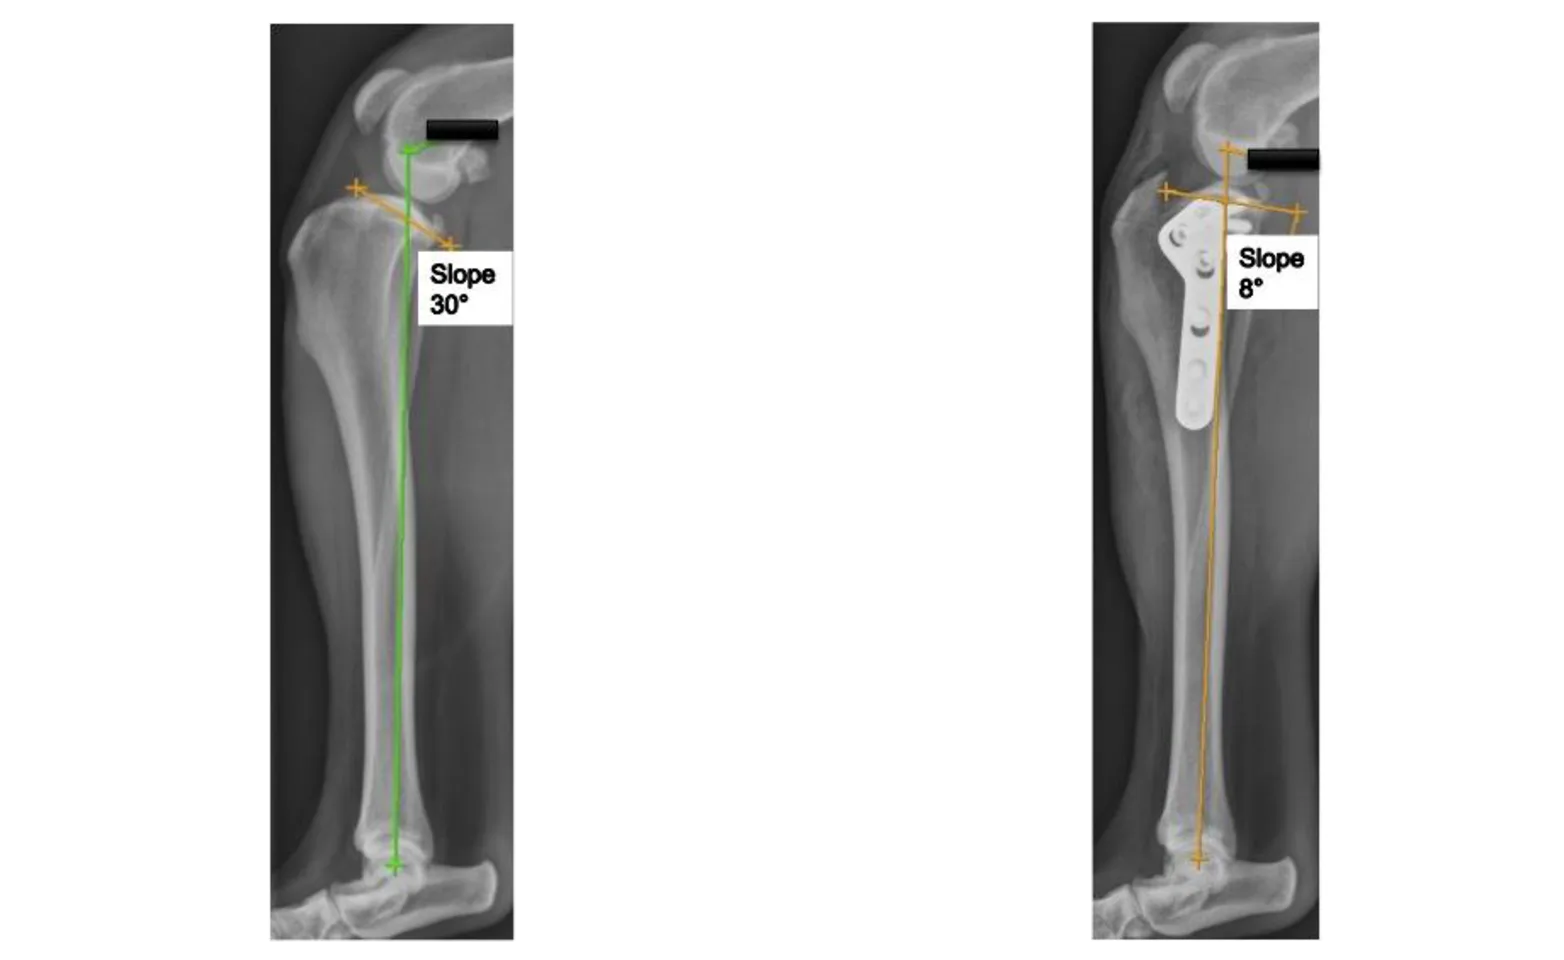

Next, a semicircular cut is made into the top portion of the tibia and the segment is rotated backward to create a flatter tibial slope. The two pieces of bone are then held in place with a stainless steel bone plate that is screwed onto the bone. See the X-rays pre and post-TPLO surgery (fig 2 [Pre-op. Steep slope.] & fig 3 [Post-op. Flatter slope]).